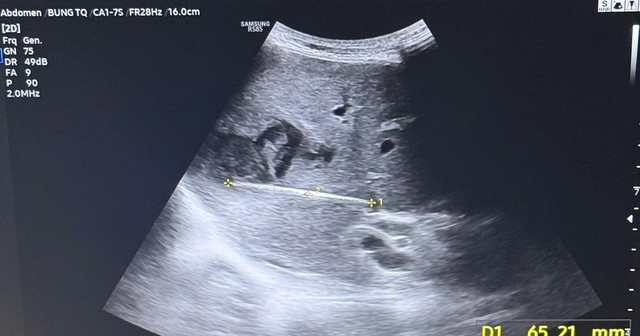

Tại bệnh viện Chợ Rẫy, kết quả siêu âm bụng ban đầu chỉ ghi nhận hình ảnh nghi ngờ áp xe gan. Bệnh nhân được nhập viện theo dõi và thực hiện lại các thăm dò hình ảnh chuyên sâu.

Qua siêu âm kiểm tra và chụp CT ổ bụng, các bác sĩ phát hiện một tổn thương bất thường trong gan với hình ảnh dị vật dài khoảng 7 cm nằm hoàn toàn trong nhu mô gan, kèm theo ổ áp xe sâu.

Nguy kịch tính mạng vì thói quen phổ biến sau bữa ăn của người Việt- Ảnh 1.

Hình ảnh kiểm tra phát hiện dị vật xuyên thấu vùng gan của người bệnh gây áp xe nghiêm trọng